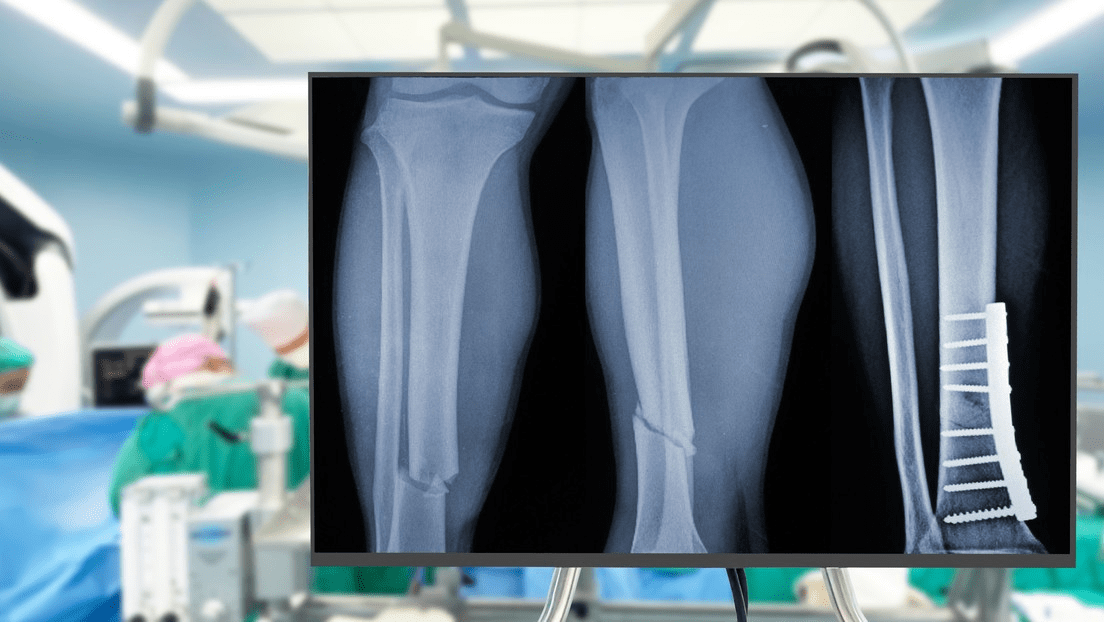

Un grupo de expertos en ortopedia de la provincia de Zhejiang (China) ha desarrollado un pegamento para huesos que es capaz de unir y fijar con precisión fracturas óseas en cuestión de tres minutos y mediante una sola inyección, reporta el portal The China Academy este lunes.

Gracias a su tecnología adhesiva, el pegamento, bautizado como Bone 02, ha logrado unir y fijar en unos pocos minutos distintos fragmentos óseos mediante una incisión de 2 a 3 centímetros que resulta mínimamente invasiva.

El material, inspirado en las ostras, representa un avance significativo respecto de los procedimientos tradicionales, que utilizan placas de metal para recuperar los huesos atendidos.